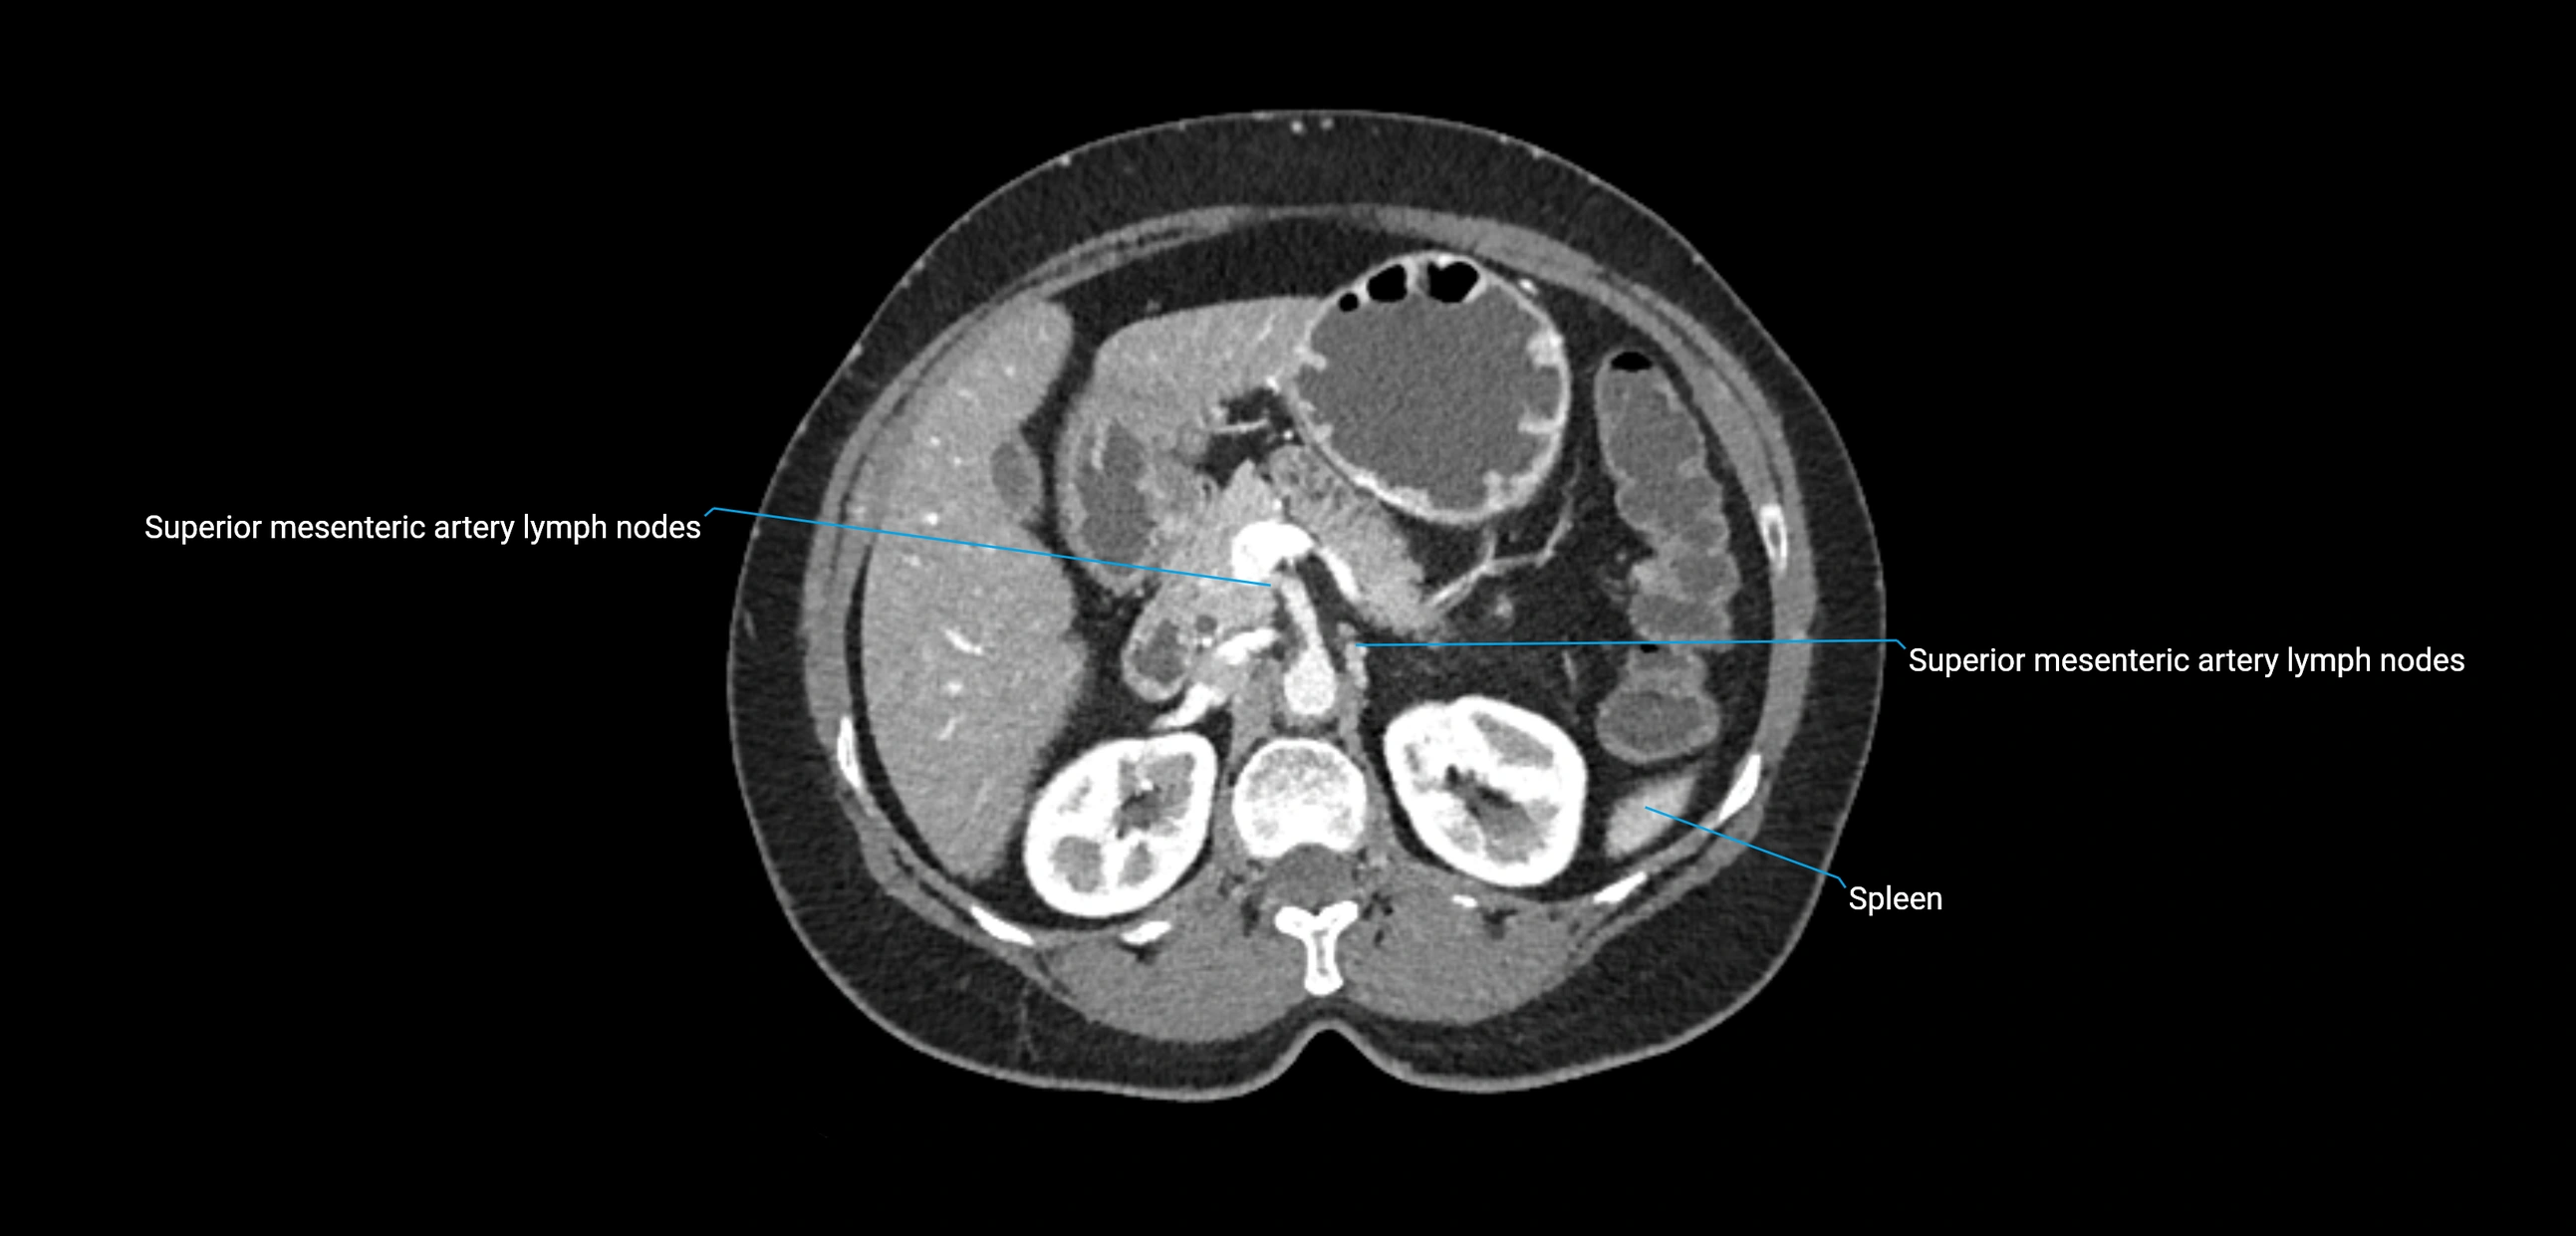

CT image

image